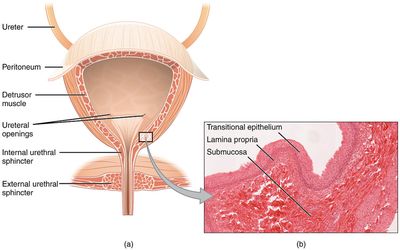

Síndrome de vejiga hiperactiva: ejercicios y remedios naturales